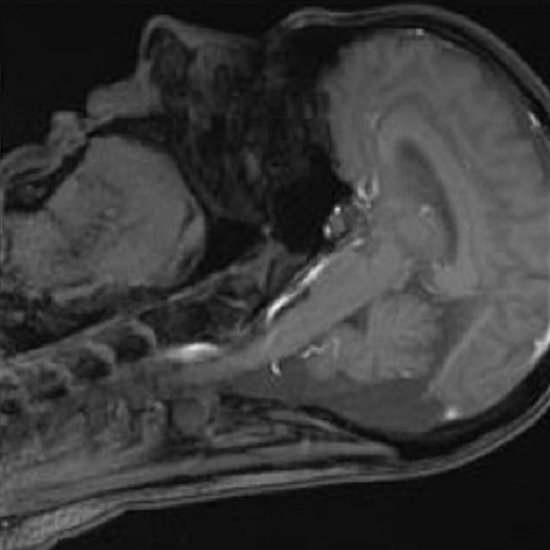

News • Darstellung von Auge und Gehirn

Metamaterialien verbessern MRT-Bildqualität

Feine Strukturen an Auge, Augenhöhle und Gehirn lassen sich im MRT oft nur ungenau darstellen. Forschende haben nun einen Weg gefunden, die Bildqualität zu erhöhen und die Scan-Dauer zu verkürzen.